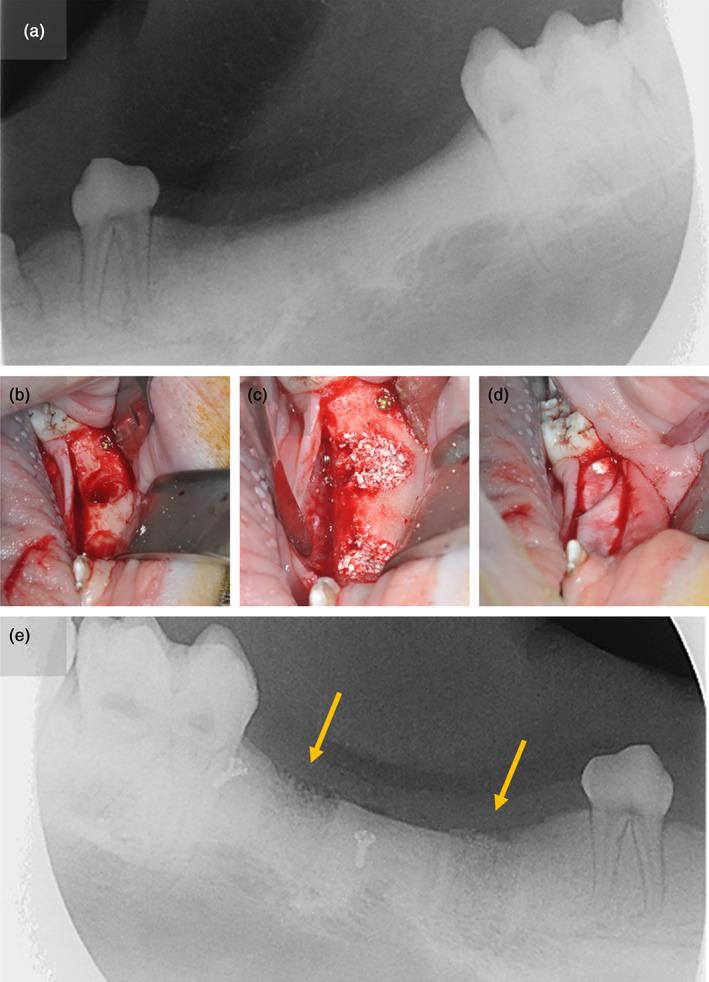

The preclinical evaluation of bone substitutes is frequently performed in artificially created defects. However, such defects do not reflect the predominant clinical application of bone substitutes for socket preservation. Hence, the goal of this animal study was to compare the performance of a xenogenic bone substitute in extraction sites versus artificial defects.

MATERIAL AND METHODS

Four study sites each were created in the mandibles of four minipigs in the region of the third premolars and first molars, respectively. On one side, fresh extraction sockets were established while contralaterally trephine defects were created in healed alveolar bone. All sites were augmented using a particulate xenogenic bone substitute, covered by resorbable membranes and allowed to heal for 12 weeks. The amounts of new bone, non-bone tissue and remaining bone substitute granules were quantified through histological and micro-CT analysis. Comparative statistics were based on t-tests for two samples and ANOVA with the level of significance set at α = 0.05.

RESULTS

Histomorphometric data from only two animals could be quantitatively analyzed due to difficulty with identifying the surgical sites. The percentage of newly formed bone ranged between 53.2% ± 5.6% for artificial defects and 54.9% ± 12.4% for extraction sites. With the exception of ANOVA indicating a greater amount of non-bone tissue in extraction sites as compared to artificial sites (p = 0.047), no statistically significant differences were observed. Micro-CT scans showed patterns similar to the ones observed in histomorphometry. As extraction sites could be identified only in two micro-CT reconstructions, quantitative assessment was not undertaken.

CONCLUSIONS

Despite the comparable performance of bone substitute material in artificial defects and extraction sites found here, the data gathered with this experiment was insufficient for showing equivalence of both approaches.